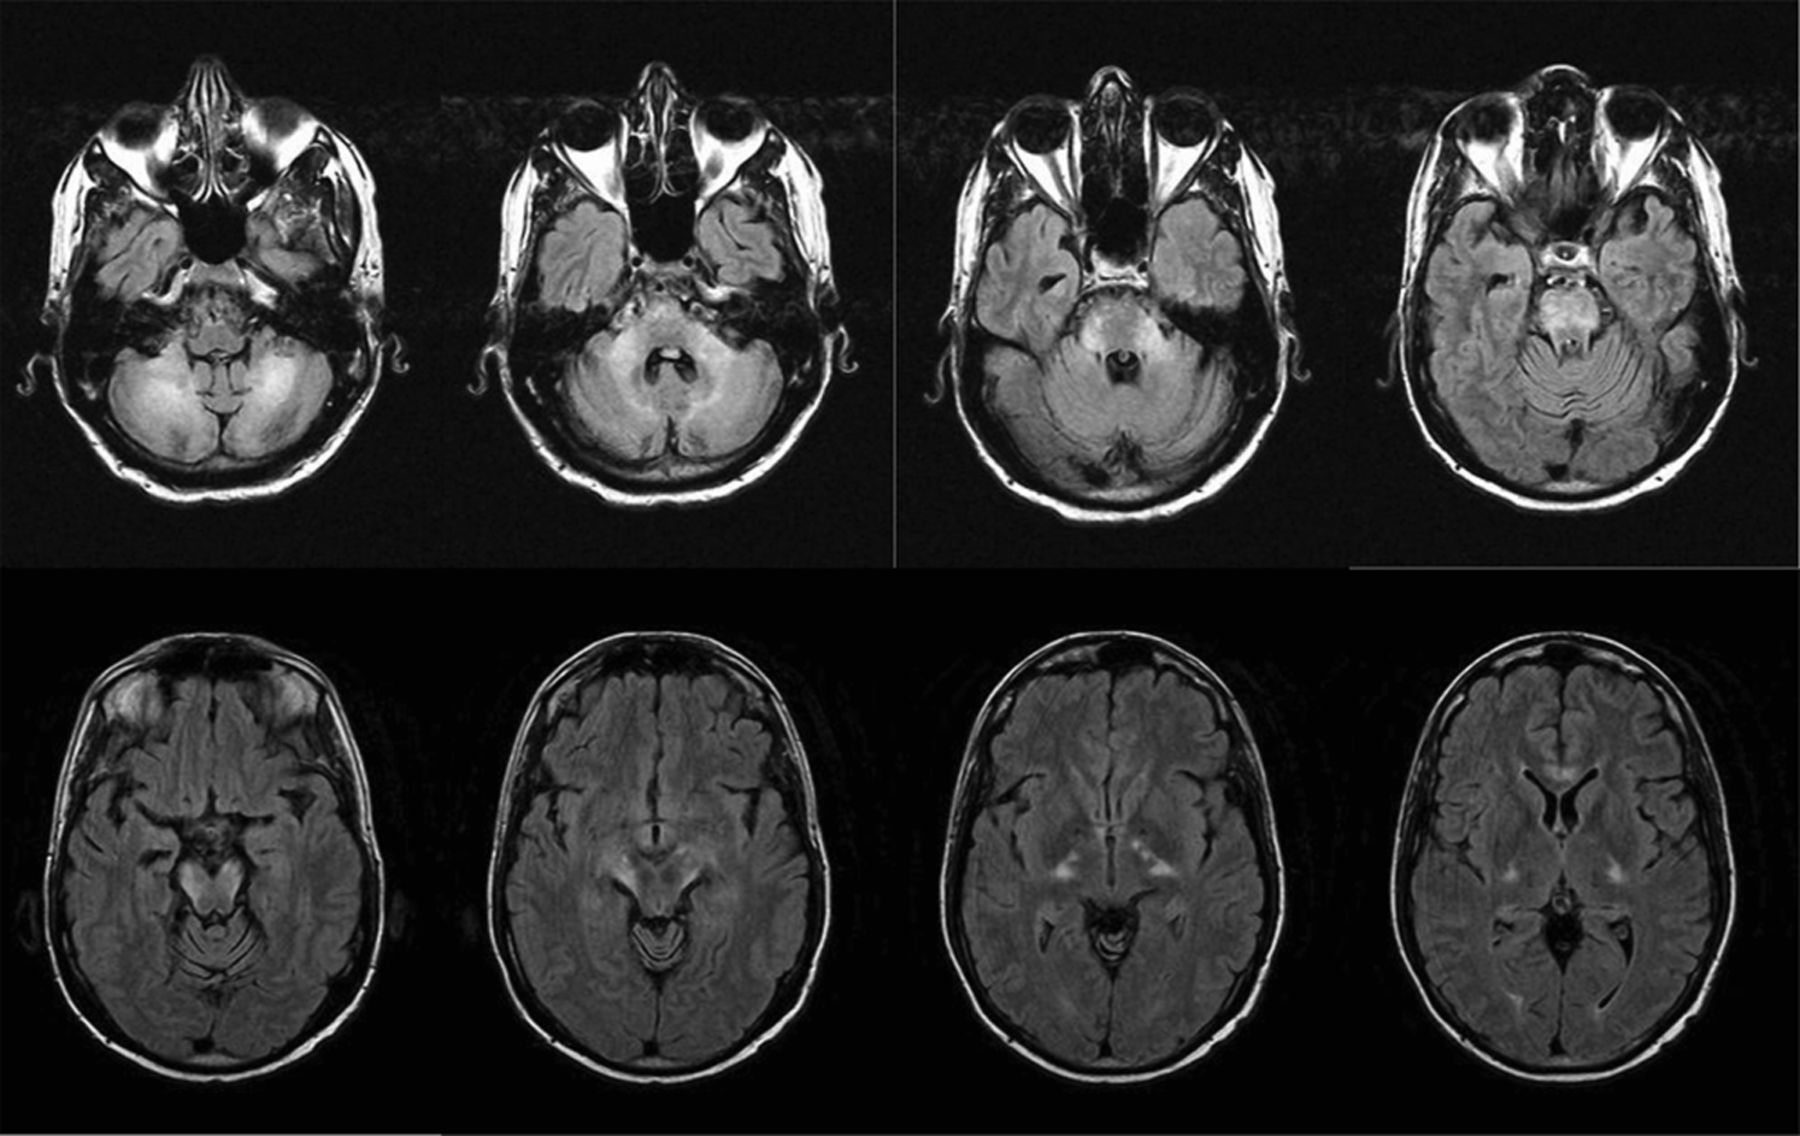

42岁的男子与艾迪生疾病呈现给急诊室1年的步态蹒跚。一个同父异母的兄弟有癫痫和行走困难,在6岁时去世。另一个同父异母兄弟长期以来步态障碍。在3到4个月,他与刚度,步态变得更糟共济失调、构音障碍。神经系统检查证明眼跳追求,眼颤振,严重痉挛状态,周围神经病变,反射亢进,阵挛,双边伸肌足底反射,标志着测距不准,dysdiadochokinesia。他站在一个标志着俯身向前弯曲膝盖。MRI显示在图1和图2。very-long-chain脂肪酸的血浆浓度,这是一个通用测试过氧化物酶病障碍,高架,证实诊断罹(ALD)。Very-long-chain脂肪酸也升高幸存的哥哥的等离子体。成人大脑退化是极其罕见的。这是x染色体过氧化物酶病障碍突变造成的ABCD1基因位于中Xq28和涉及到神经系统,肾上腺皮质,睾丸间质细胞和睾丸。1,2